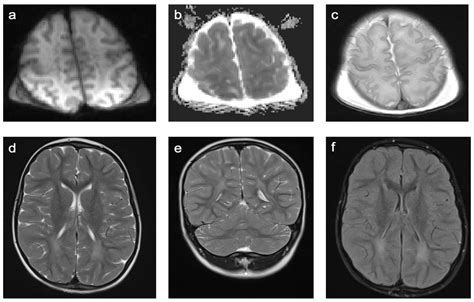

Discovering that you or a loved one has lesions on the brain can be an incredibly alarming experience. The term itself is broad, referring to any area of the brain that appears abnormal when compared to healthy tissue on a medical imaging scan, such as an MRI or CT scan. While the word "lesion" may sound ominous, it is simply a medical descriptor for a finding—it does not automatically equate to a diagnosis of cancer or a terminal illness. Understanding what these spots represent, how they are detected, and what the diagnostic process entails is crucial for navigating this complex medical landscape with clarity and reduced anxiety.

At its core, a brain lesion is an area of damage or abnormal tissue. These spots can vary significantly in size, shape, and location within the brain. Because the brain is a highly complex organ where different regions control specific functions—such as movement, speech, memory, and emotion—the impact of a lesion depends entirely on where it is situated and what caused it in the first place.

When a radiologist reviews brain imaging, they look for areas that show different signal intensities than the surrounding, healthy brain matter. These differences can be caused by various underlying processes, ranging from inflammation and infection to vascular issues or tumors. Because the causes are so diverse, it is impossible to determine the nature of a lesion based solely on its appearance on a scan; further investigation is almost always required.